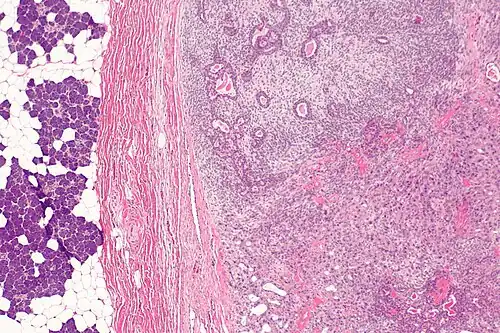

Histologicamente, apresenta-se como um adenoma pleomórfico (componente benigno) associado a um componente carcinomatoso que pode ser um carcinoma do ducto salivar, carcinoma mioepitelial (usualmente de baixo grau), adenocarcinoma (usualmente de alto grau, do tipo carcinoma do ducto salivar ou adenocarcinoma não especificado, com a presença de diferenciação escamosa, mucoepidermoide ou polimórfica) ou carcinoma epitelial-mioepitelial.[1]